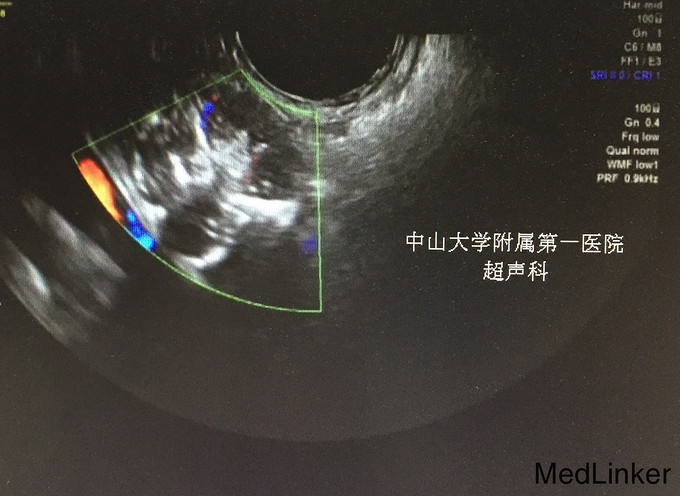

查体:生命体征平稳;双侧乳腺发育稍差。妇检:外阴呈女性生殖特征,阴蒂肥大,可见尿道开口;阴道外口可见,无性生活史,未内诊。肛查示子宫小,盆腔右侧可及包块。 辅查:2015-08-15妇科B超示:子宫小,左侧卵巢内未见明显卵泡结构;右侧附件区囊性肿块,待排畸胎瘤(43mm*30mm)。 2015-08-24查染色体示46XY,t(4;20)(q27;p13)。 2015-09-28我院查盆腔MR示双侧附件肿块,性质待定,考虑卵巢来源;阴茎发育短小,子宫小,符合双性畸形改变。

诊断:两性畸形 治疗:请我院资深超声科主任医师复查妇科B超示双侧两性母细胞瘤可能。查腹部MR:1.右侧附件区囊实性肿块,左侧附件区实性肿块,性质待定,考虑卵巢来源肿瘤。 2.阴茎发育短小,子宫稍小,符合双性畸形改变。 3.双侧肾脏及输尿管、膀胱MRI扫描未见异常。 4.上腹部MRI扫描未见异常。 请儿科教授会诊,46XY性发育障碍,意见:女性表型含Y染色体者发生性腺恶性肿瘤可能性大,建议腹腔镜性腺切除。查皮质醇8AM正常及ACTH 8AM,均正常。行腹腔镜下双侧性腺肿瘤切除术+双输卵管切除术。术中冰冻结果:良性。